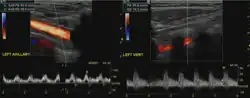

Additional images